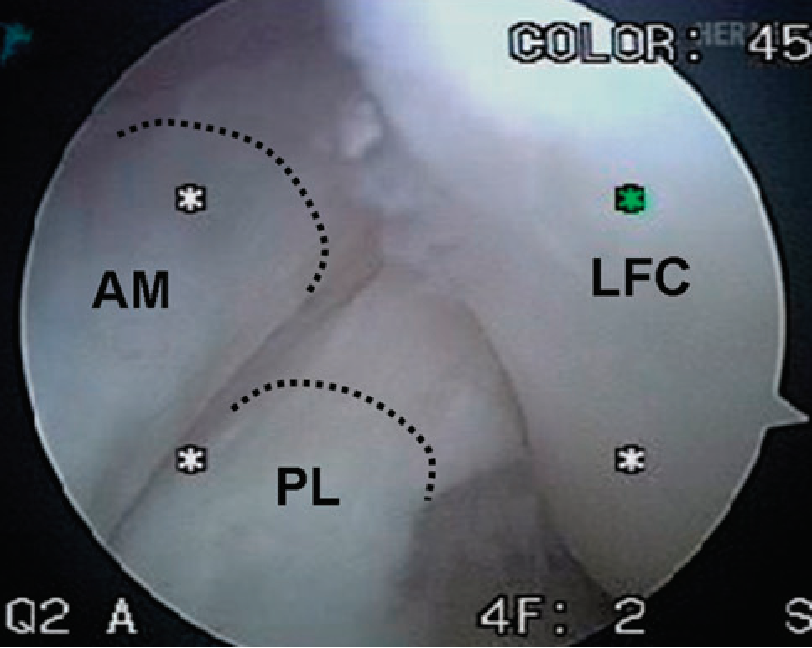

胎儿膝关节显示:两个功能束(AM,PL)

LFC为股骨外髁

关节镜显示AM,PL

伸直时AM,PL的股骨点垂直排列,两束平行。

屈曲90°时,AM,PL的股骨点平行,两束交叉

膝关节屈曲90 °时PL松弛,而伸直时PL紧张状态